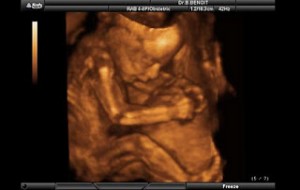

Bebeğin Boyutu: 43.7 cm, 1.9 kg

Hamileliğin (Gebeliğin) 35. Haftası Resim ve Video;